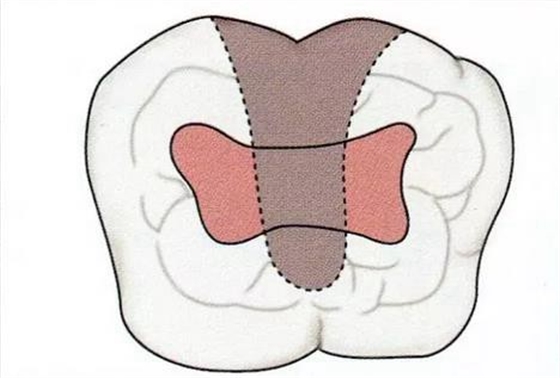

▼圖16-4

圖16-4進(jìn)行牙齒分割時(shí),如圖所示一樣,要確保分割去除的牙根邊緣不會(huì)殘留在牙槽中間骨脊。如果有邊緣殘留,會(huì)造成軟組織發(fā)紅,引發(fā)炎癥。

▼圖17

圖17將右上6近中頰側(cè)根拔除,考慮到修復(fù)物清潔性的情況下進(jìn)行備牙。牙齒分割后如果有邊緣殘留,就會(huì)使切割面的牙齦發(fā)紅無法治愈。